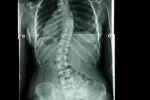

Tratamiento de la escoliosis

Opciones para el tratamiento de la escoliosis

En las decisiones terapéuticas para las deformidades vertebrales, se consideran varios factores: edad del paciente, gravedad y localización de la curva, etiología (causas) de la misma, y presencia de otras patologías asociadas. Los objetivos básicos del tratamiento de la escoliosis son: